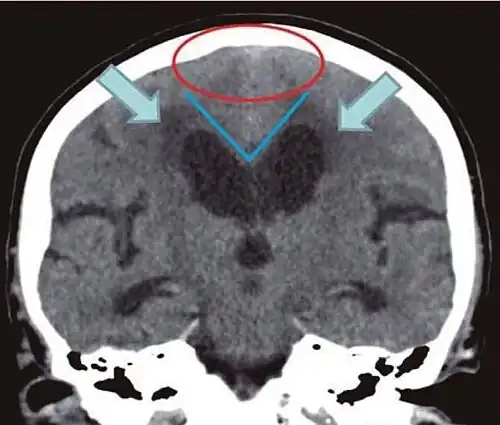

Typical imaging findings in normal pressure hydrocephalus versus brain atrophy.[21]

Normal pressure hydrocephalus Brain atrophy

Preferable projection Coronal plane at the level of the posterior commissure of the brain.

Modality in this example CT MRI

CSF spaces over the convexity near the vertex (red ellipse ) Narrowed convexity ("tight convexity") as well as medial cisterns Widened vertex (red arrow) and medial cisterns (green arrow)

Callosal angle (blue V) Acute angle Obtuse angle

Most likely cause of leucoaraiosis (periventricular signal alterations, blue arrows ) Transependymal cerebrospinal fluid diapedesis Vascular encephalopathy, in this case suggested by unilateral occurrence